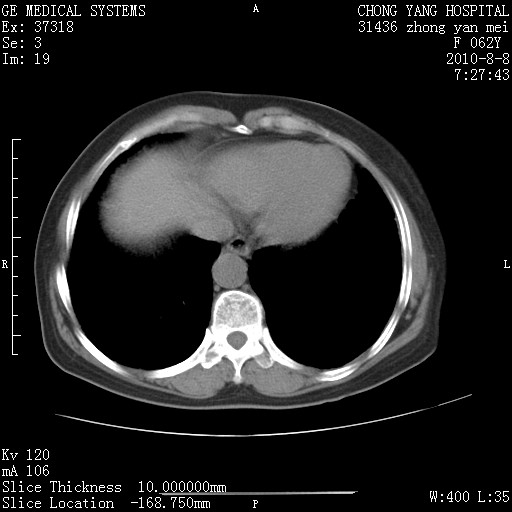

标题: CT28269:F62Y咳嗽胸痛数月。 [打印本页]

标题: CT28269:F62Y咳嗽胸痛数月。

两肺弥漫性间质纤维化伴继发性支扩。

考虑特发性肺间质纤维化

考虑两肺间质性肺炎并肺间质纤维化。

双肺间质纤维化合并感染、肺气肿

双肺间质纤维化

两肺间质纤维化并牵拉性细支气管扩张。

考虑两肺间质性肺炎并肺间质纤维化,肺气囊形成。

两肺间质改变,纵隔淋巴结肿大,需要考虑结节病的可能。